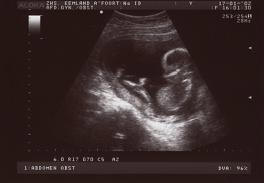

De eerste foto waarop Lars te zien is. Wij wisten alleen nog niet dat het Lars zou gaan worden.

Hier heeft Lars ruim 9 maanden in doorgebracht.